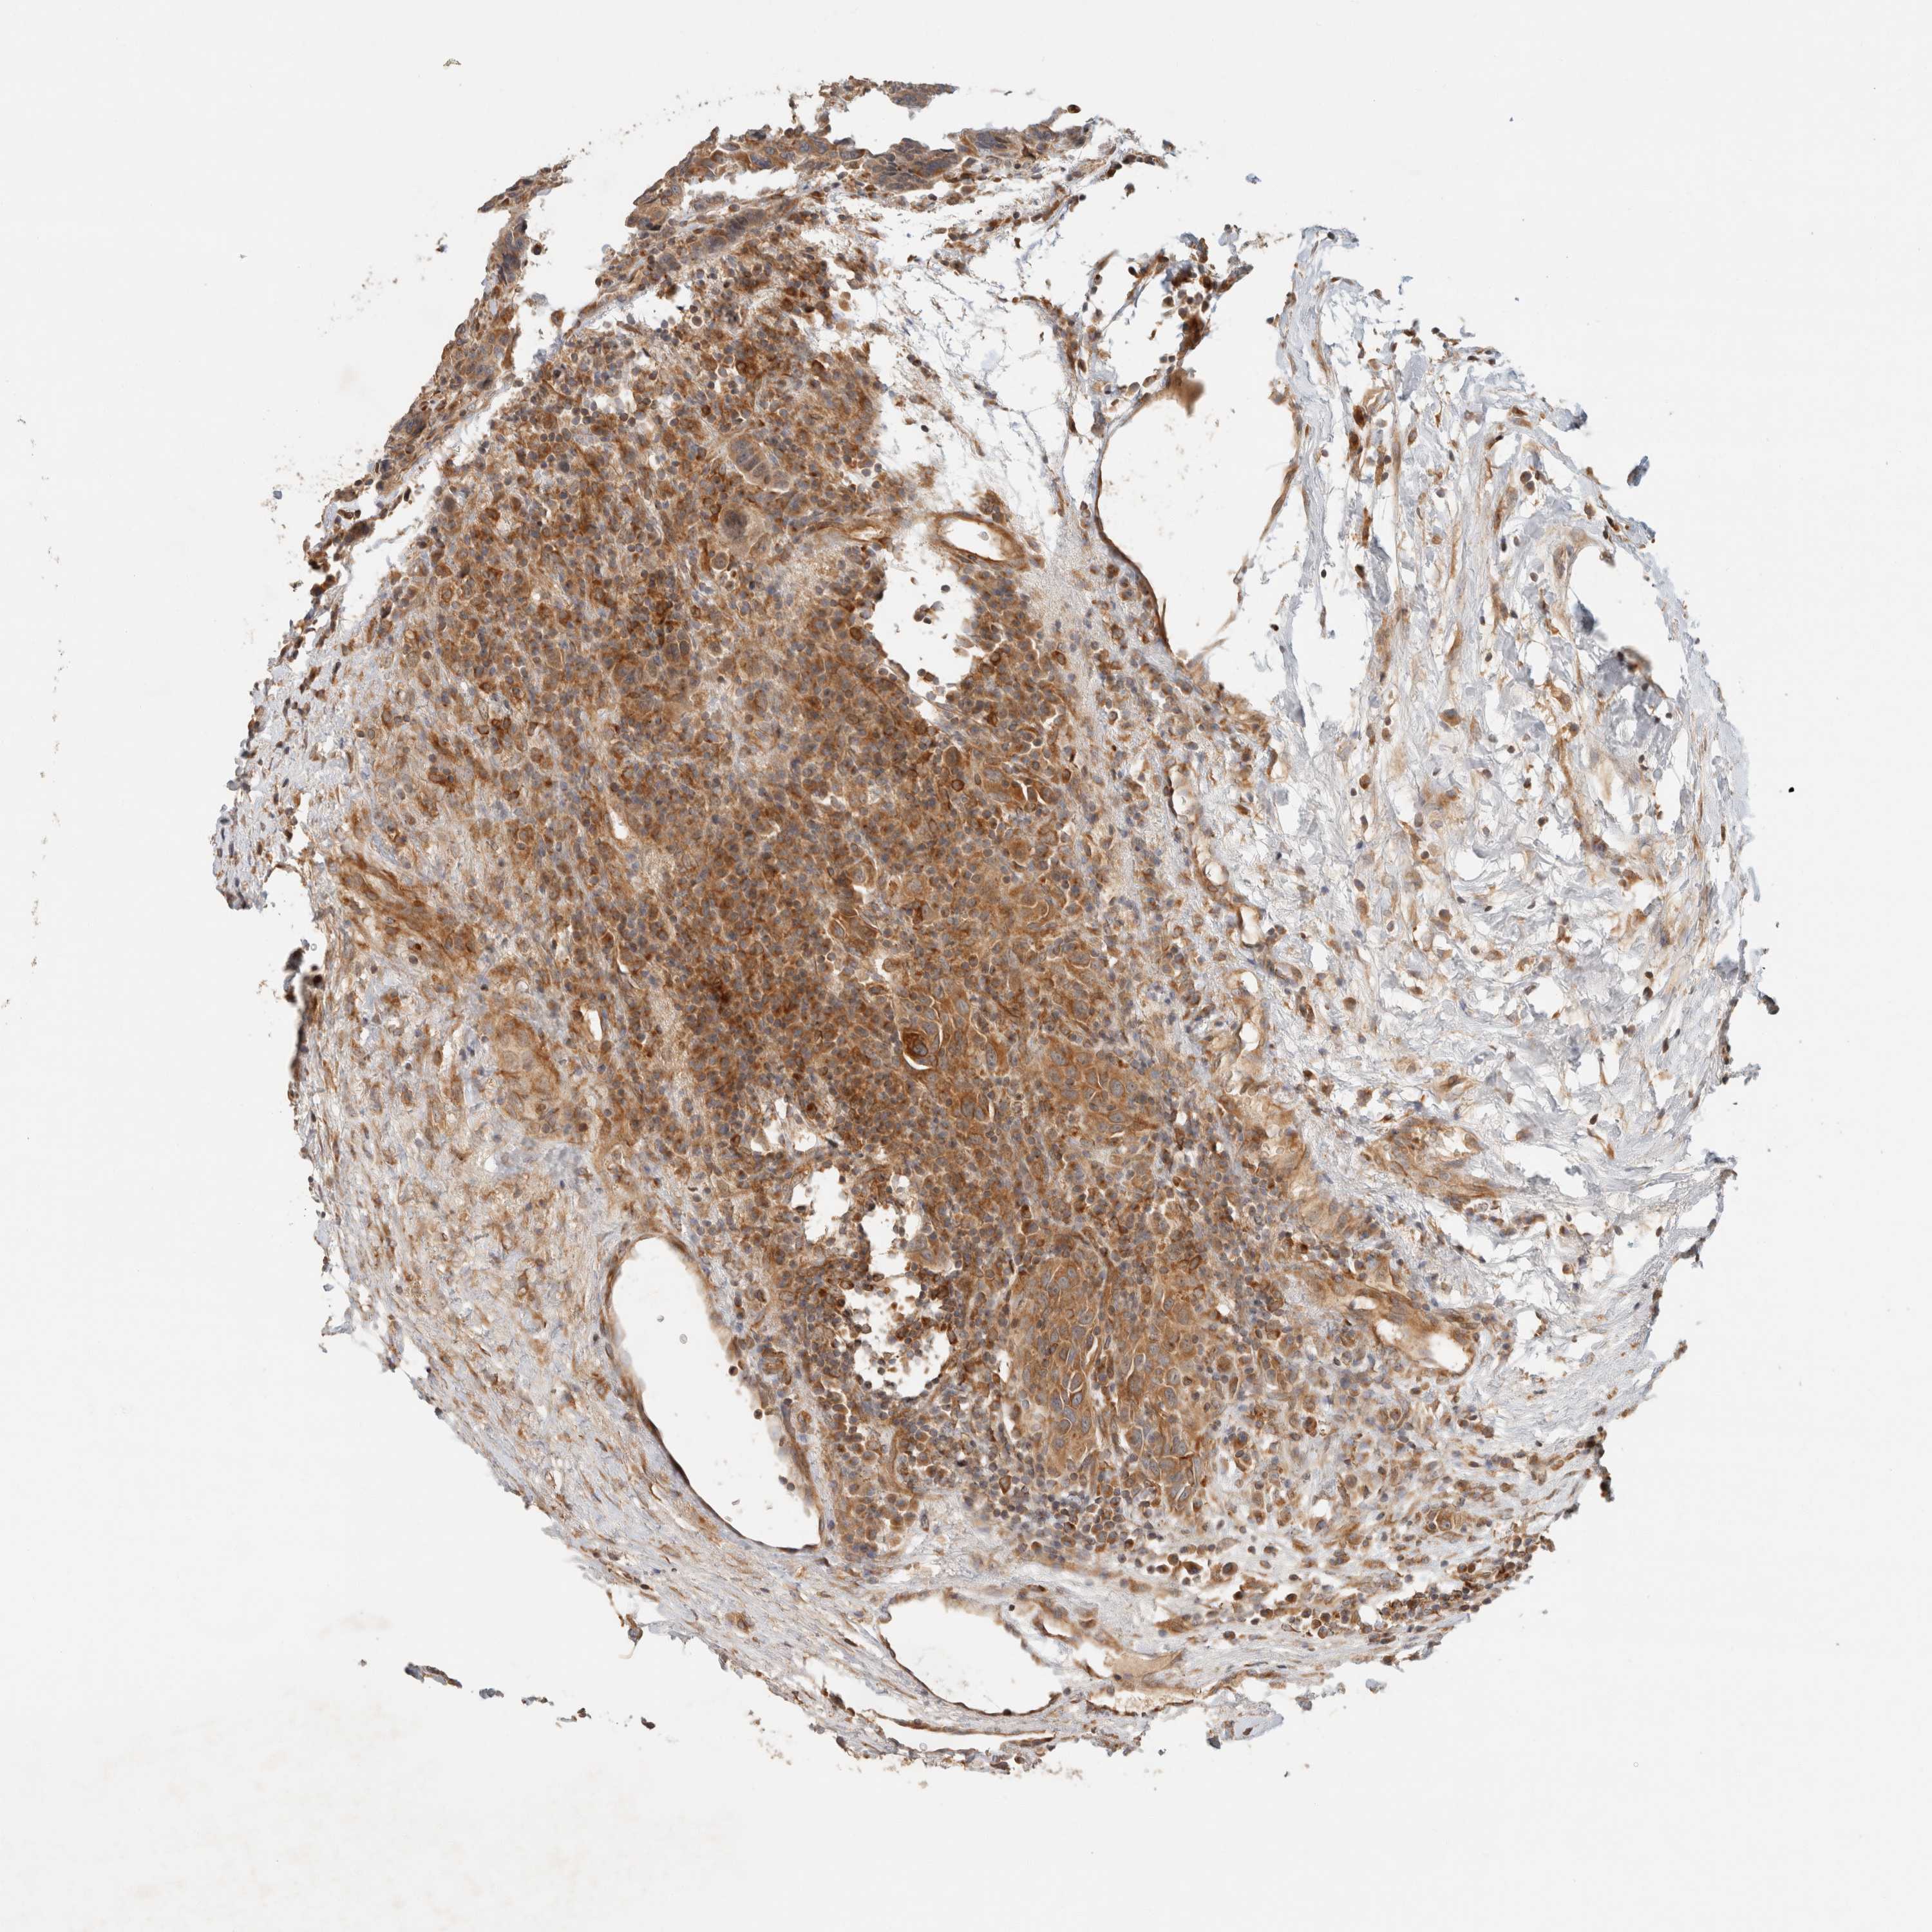

CANCER BREAST CANCER Show tissue menu

BRCA TCGA BRCA VALIDATION PROTEIN EXPRESSION

ANTIBODIES

AND

VALIDATION